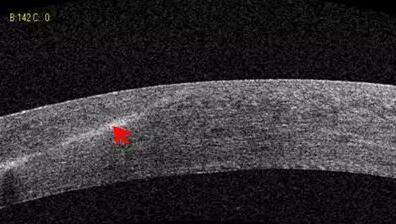

1、角膜分层观察 OCT 轴向分辨率高达5μm,远高于UBM(20--60μm),可识别出泪膜、上皮层、前弹力层、基质层、后弹力层/内皮层

2、角膜厚度评估,角膜水肿、瘢痕、混浊、溃疡、异物、炎症、胬肉等断层观察

3、角膜屈光手术后角膜瓣观察、角膜厚度评估等

4、后弹力层角膜内皮移植术(DSEK)、板层角膜移植术、白内障术后内皮层脱落等术后观察